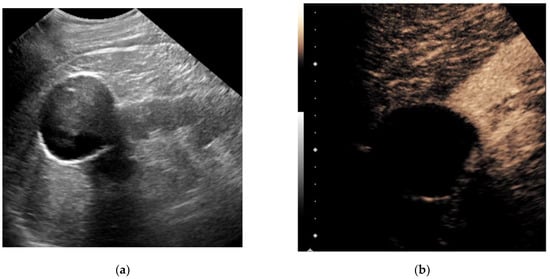

3.1. Contrast-Enhanced Ultrasound